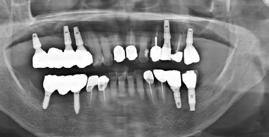

9. ábra: Különböző stádiumnál készített röntgenfelvételek.

10. ábra: Kontroll 18 hónappal később.

lás vált szükségessé, azt sikertelenségnek vettük. Az implantátumok sikerességi aránya 100%-os volt 18 hónap után (9–10. ábra). A előre legyártott azonnali pótlások protetikai sikerességi aránya 90%-os volt. Két esetben a korona levált a felépítményről az első hat hónap során. Egy összefoglaló elemzésben a szerzők összehasonlították a különböző implantátumbehelyezési és terhelési protokollokat (12). A cikkben az azonnali implantáció és azonnali terhelés 98,4%-os

sikerességi aránnyal szerepel. A hagyományos protokollok, ahol a késői implantációt hagyományos késői terhelés követi, a sikerességi arány 97,7%. Meg kell jegyeznünk azonban, hogy a szisztematikus áttekintésbe bevont cikkek között a bizonyítékok szintjében néha lényeges különbségek voltak, amikor az egyes protokollokat összehasonlították. Az azonnali implantáció adatai klinikailag dokumentált adatokra korlátozódtak.